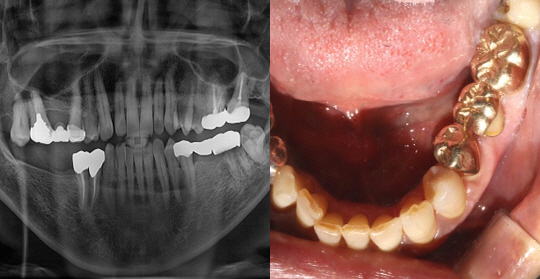

(66세 여 환자)